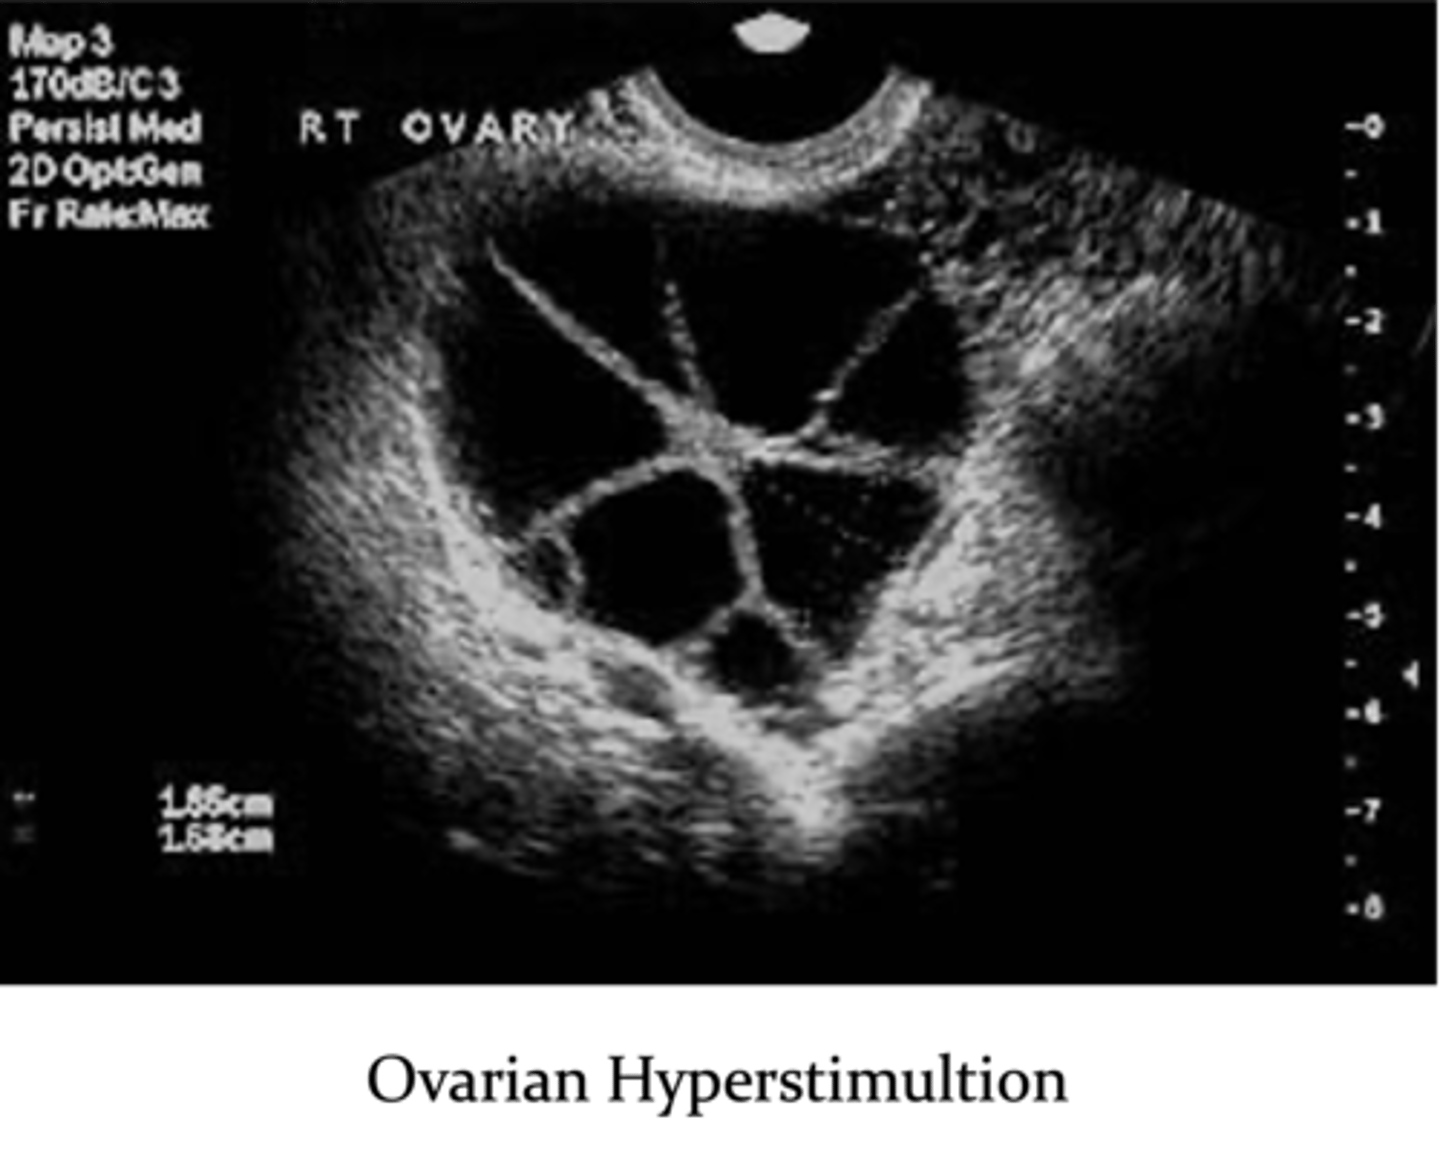

What are complications with assisted reproductive technology?

1. ovarian hyperstimulation

2. multiple gestations (25% chance)

3. ectopic pregnancy